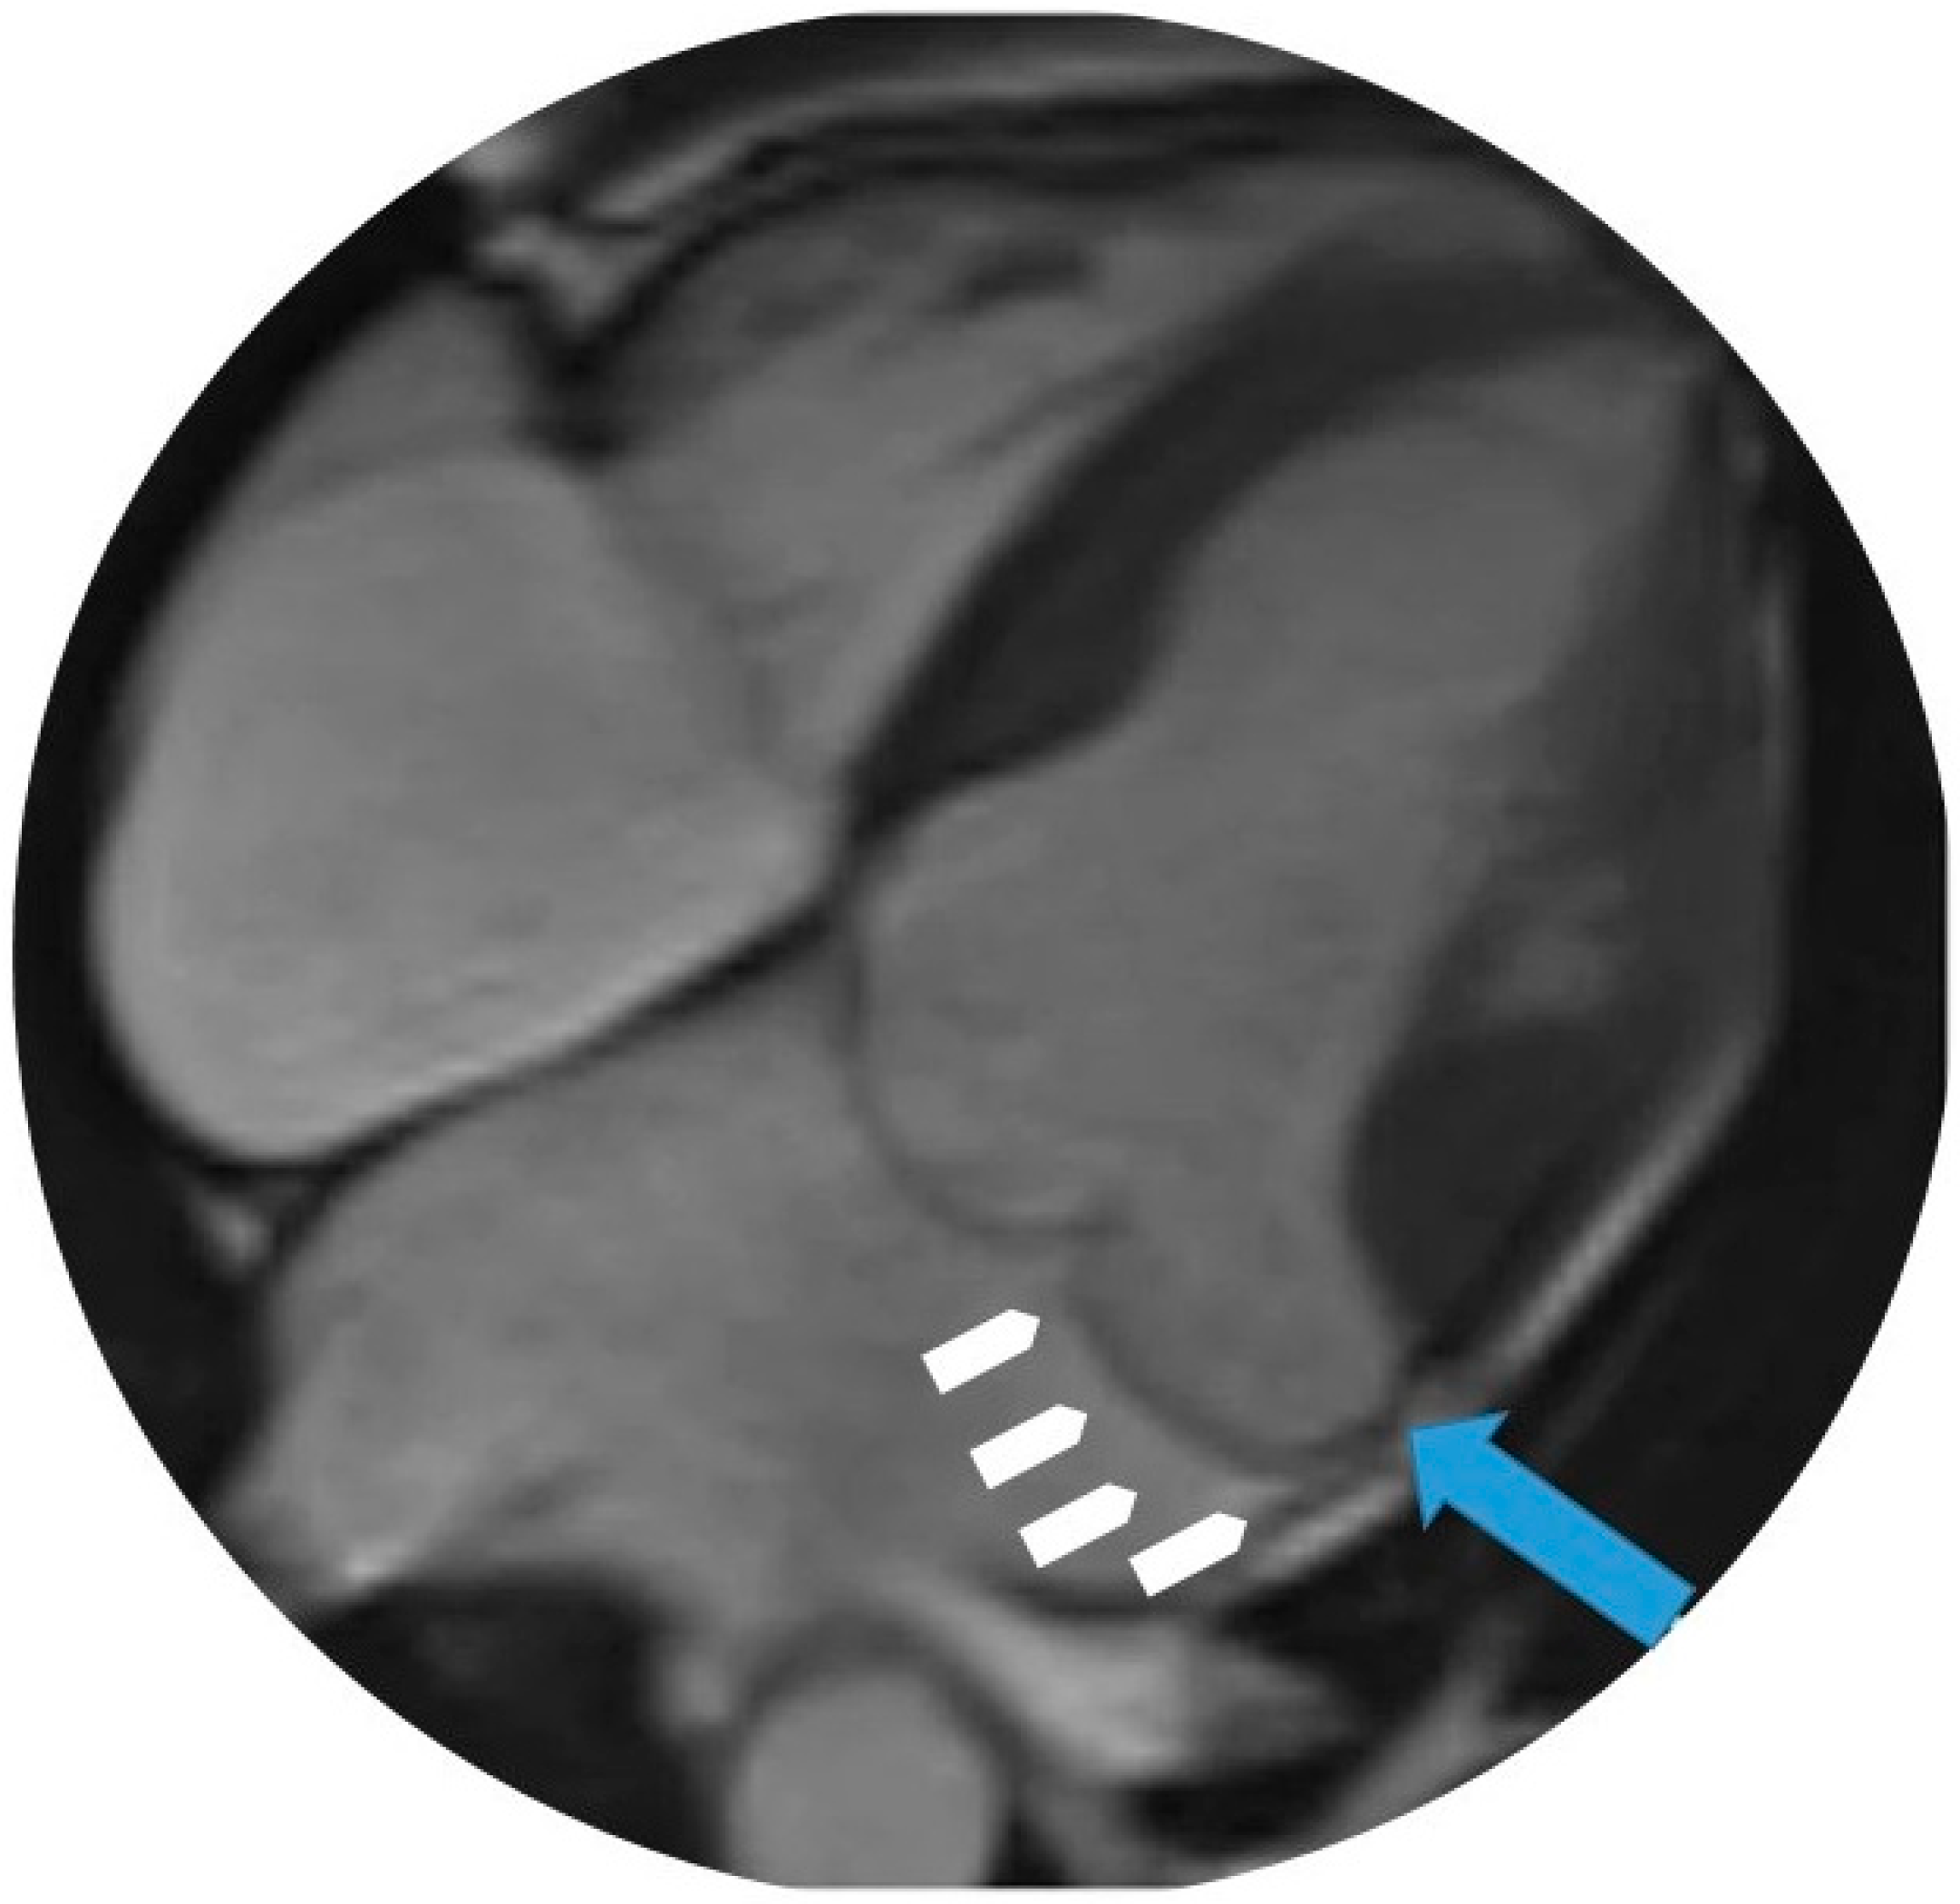

4.4. Cardiovascular Magnetic Resonance (CMR)